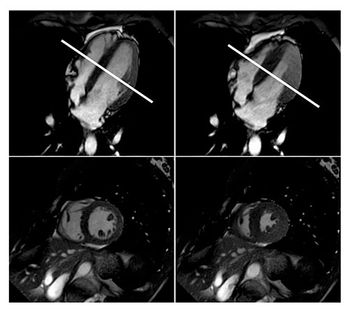

CHICAGO-MRI shows significant changes to the heart of elite free divers.